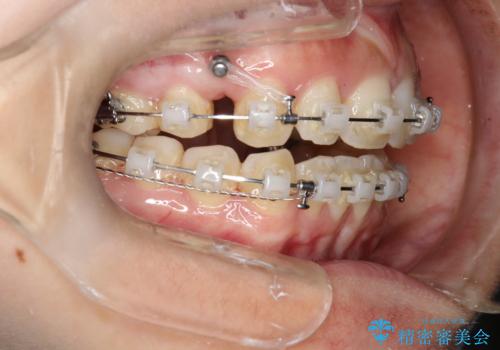

出っ歯で口が閉じずらい ワイヤーによる抜歯矯正

- 出っ歯で口が閉じずらくて、前歯でものかが噛み切れないとのことで来院されました。

上顎の前歯が前方に傾斜して、下顎の前歯と接触していない状態でした。

上顎の前から4番目の歯を両側抜歯して前歯を後方に移動させる計画としました。

前歯がしっかり下がることで、上下の前歯があわさり食事もしやすくなったと言っていただきました。